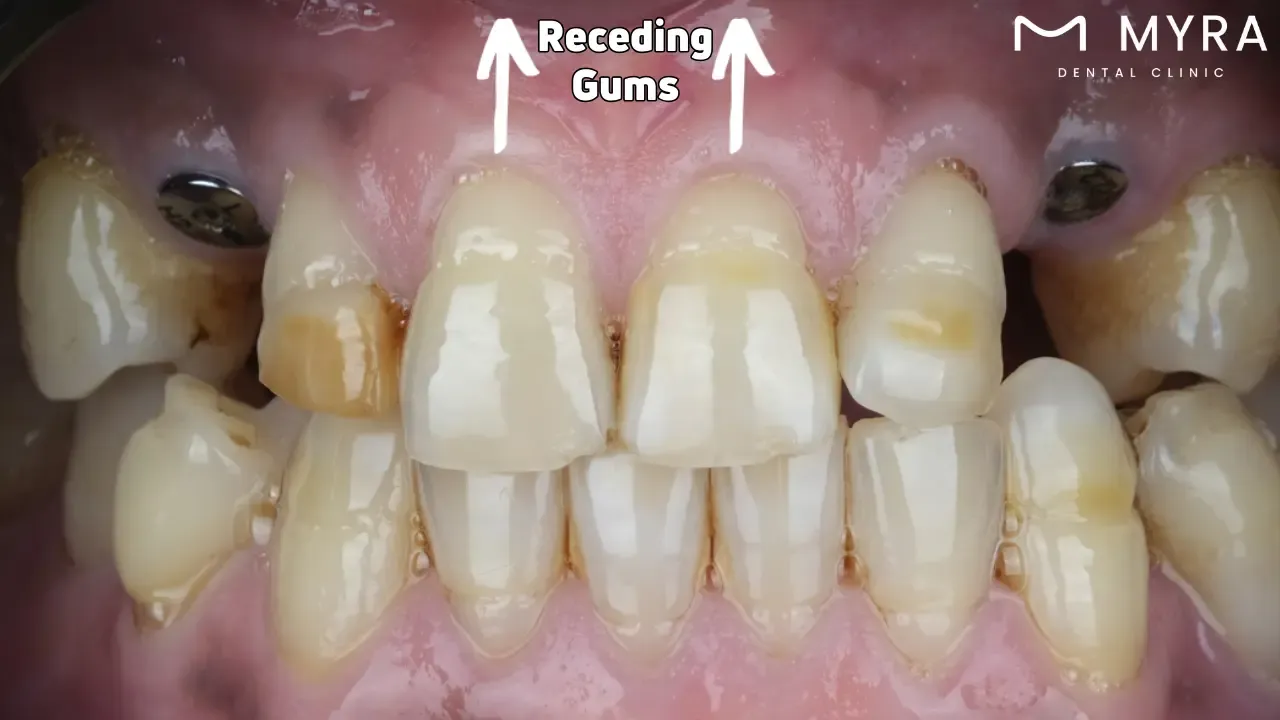

13. Receding Gums

Receding gums or gingival recession, is a dental disease where more of the tooth or its root is seen due to wear and tear on the gum tissue around the teeth. The disorder causes "pockets" or spaces between teeth and gum lines, facilitating the growth of bacteria that cause illness.

Gum recession is caused by hormonal changes, heredity, excessive brushing, periodontal disease, poor oral hygiene, smoking, teeth clenching and grinding, crooked or misaligned teeth, and piercings. Gum recession is primarily caused by bacterial gum infections that erode gum tissue and the bone supporting the teeth. Gum recession is caused by overly vigorous tooth brushing or by using a toothbrush with firm bristles, eroding tooth enamel. Minimal brushing and flossing lead to plaque accumulation, contributing to gum recession and gum disease. Certain individuals are predisposed to recession and gum disease.

Hormone fluctuations, including during menopause, adolescence, and pregnancy, make gums more prone to recession and more susceptible to changes in hormone levels. Gum recession is caused by gum disease, a result of smoking or using other tobacco products. Gum recession results from excessive clenching or grinding, which puts pressure on the gums and teeth. Improper positioning of the teeth exerts too much tension on the bone and gums, leading to recession. Piercements on the tongue or lips irritate the gums and destroy the tissue, which results in recession.

Receding gums leads to several dangerous dental problems if they are not corrected, including increased sensitivity, cavities and tooth decay, gum disease progression, tooth mobility, and cosmetic concerns. Increased sensitivity to hot, cold, sweet, or acidic foods and beverages results from exposed tooth roots. They are more prone to cavities and decay since the exposed roots are not covered in enamel. Gum recession produces pockets where bacteria grow, worsening gum disease and causing more tissue and bone loss. Teeth become loose and detach when the supporting bone and gum tissue weaken and proper treatment is not received. Teeth that appear longer than typical due to Receding Gums have an impact on how the smile looks which affects social interactions and self-confidence.

Taking care of the root problem is necessary when treating receding gums. Enhancing dental hygiene habits, switching to a gentler toothbrush, and giving up tobacco use are helpful in moderate cases. Professional therapies such as gum grafting surgery to replace lost tissue, scaling and root planing (a deep cleaning technique), or the use of regenerative materials to promote the formation of new bone and gum tissue is necessary for more severe instances. Periodic dental examinations are crucial for tracking gum health and identifying early indications of recession before they worsen.